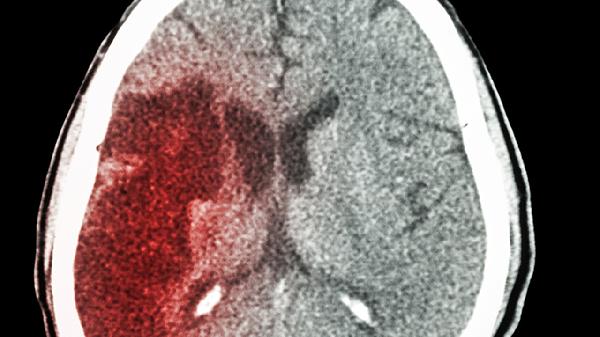

四、必须就医的红色警.报

当出现突发剧烈头痛、单侧肢体无力、说话含糊不清时,要立即拨打急救电话。脑卒中的黄金抢.救时间只有4.5小时,每延误1分钟就有190万个脑细胞死亡。